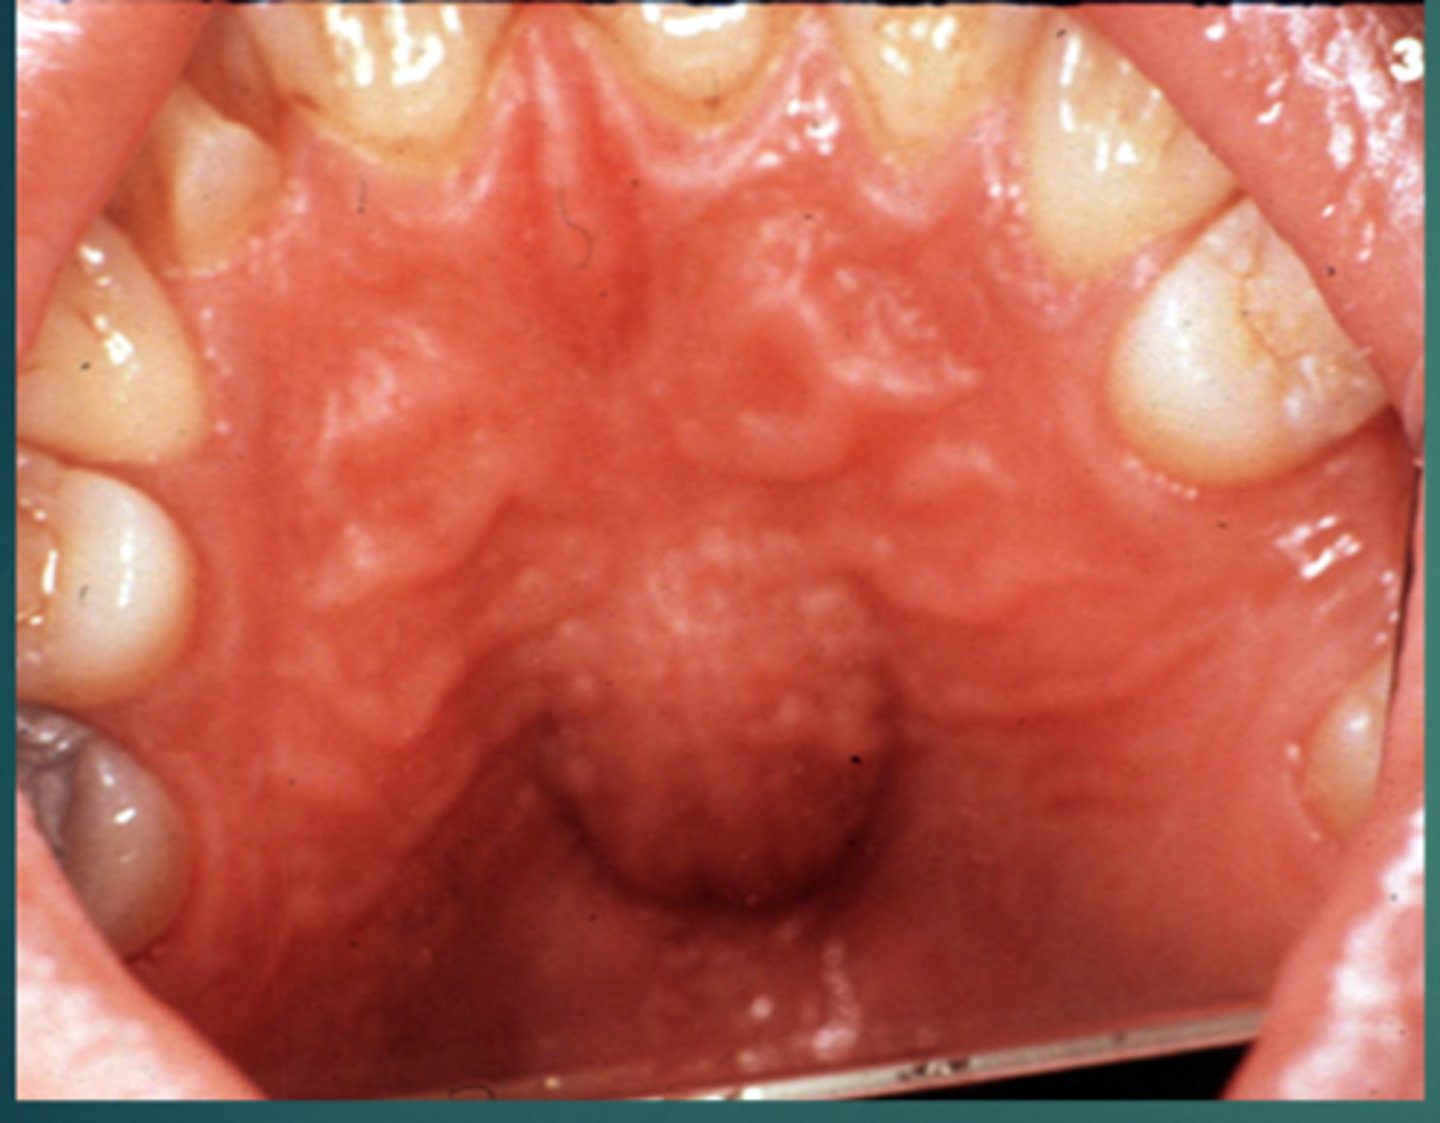

What is the common location of a median palatal cyst?

1. midline of hard palate - behind incisive papilla

What are clinical features of median palatal cysts?

swelling at midline of hard palate (if large)

What are radiographic features of median palatal cysts?

well-defined unilocular radiolucency at midline hard palate